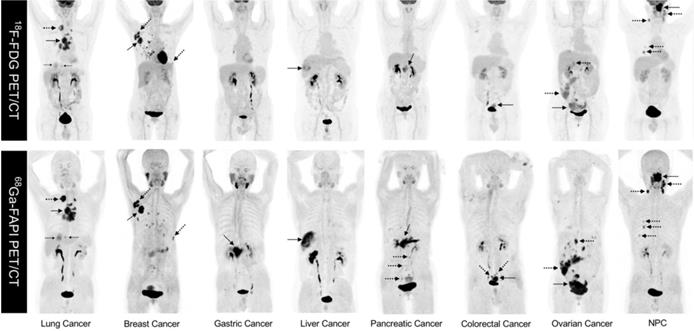

As FAPI is a novel PET tracer in cancer imaging, it is critical to evaluate lesion detection rates and diagnostic efficacy for FAPI compared with 18F-fluorodeoxyglucose (18F-FDG), the dominant tracer in oncology. To the best of our knowledge, Chen et al. conducted the first head-to-head study comparing 68Ga-FAPI-04 and 18F-FDG PET/CT in a cohort of 75 patients (54 patients identified at initial assessment and 21 patients with recurrence detection) with 12 different tumor entities. This prospective study demonstrated that 68Ga-FAPI-04 had a higher sensitivity as compared with 18F-FDG in identifying primary tumors (98.2% vs. 82.1%, P = 0.021), lymph node metastases (86.4% vs. 45.5%, P = 0.004), and bone and visceral metastases (83.8% vs. 59.5%, P = 0.004) [29]. However, the limited number of patients harboring each cancer type enrolled in this study did not allow for a subgroup comparison in terms of diagnostic efficacy for the same tumor type. Representative MIP images of both 18-FDG PET/CT and 68Ga-FAPI PET/CT in 8 patients with different types of cancer are shown in Figure 1. Some studies have recently compared the diagnostic efficacy of 68Ga-FAPI and 18F-FDG in various types of tumors.

Figure 1

Representative comparison of 8 patients with different tumor entities undergoing both 18F-FDG PET and 68Ga-FAPI-04 PET imaging within less than 1 week. Solid arrows indicate primary tumors, while the dotted arrows indicate metastasis lesions. NPC: nasopharyngeal carcinoma.